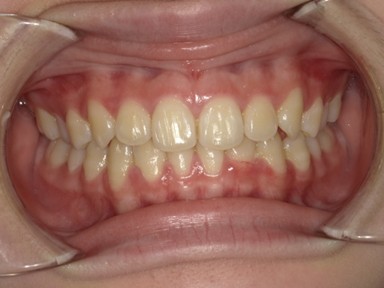

| 主訴 | 生えてきた下の永久歯が曲がっている。これから生えてくる歯も並ぶか心配。 |

| 治療内容 | マイオブレース(J1 → J2 → K3 → T4)と拡大床(BB1)を使用しました。 口腔周囲筋トレーニングも併用しました。 (抜歯:なし、ワイヤー矯正:使用せず) |

| 治療期間 | 78ヶ月(永久歯列完成まで経過観察) ※治療開始から2年間は毎月通院し、その後は3~4か月に1回の頻度で経過観察を継続。 |

| 治療回数 | 38回 |

| 想定されたリスク | 抜歯や全顎ワイヤー矯正のリスクがありました。 |